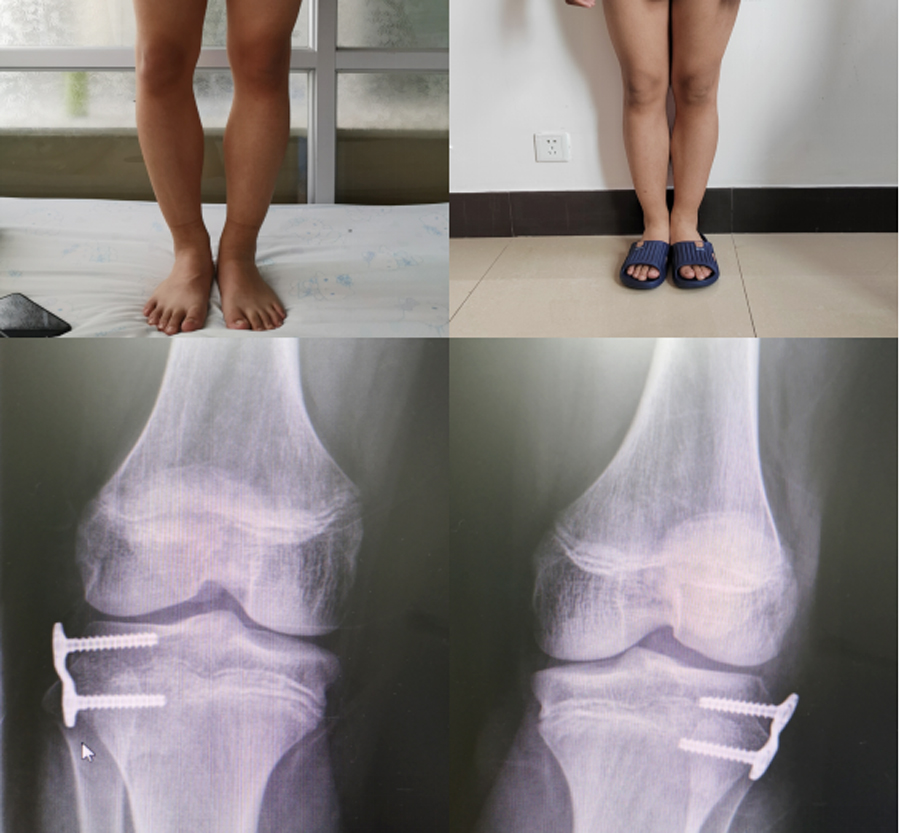

膝内翻畸形(“O”型腿)通过骺板阻滞引导性生长技术,1年后得到纠正,术后即可下地行走。